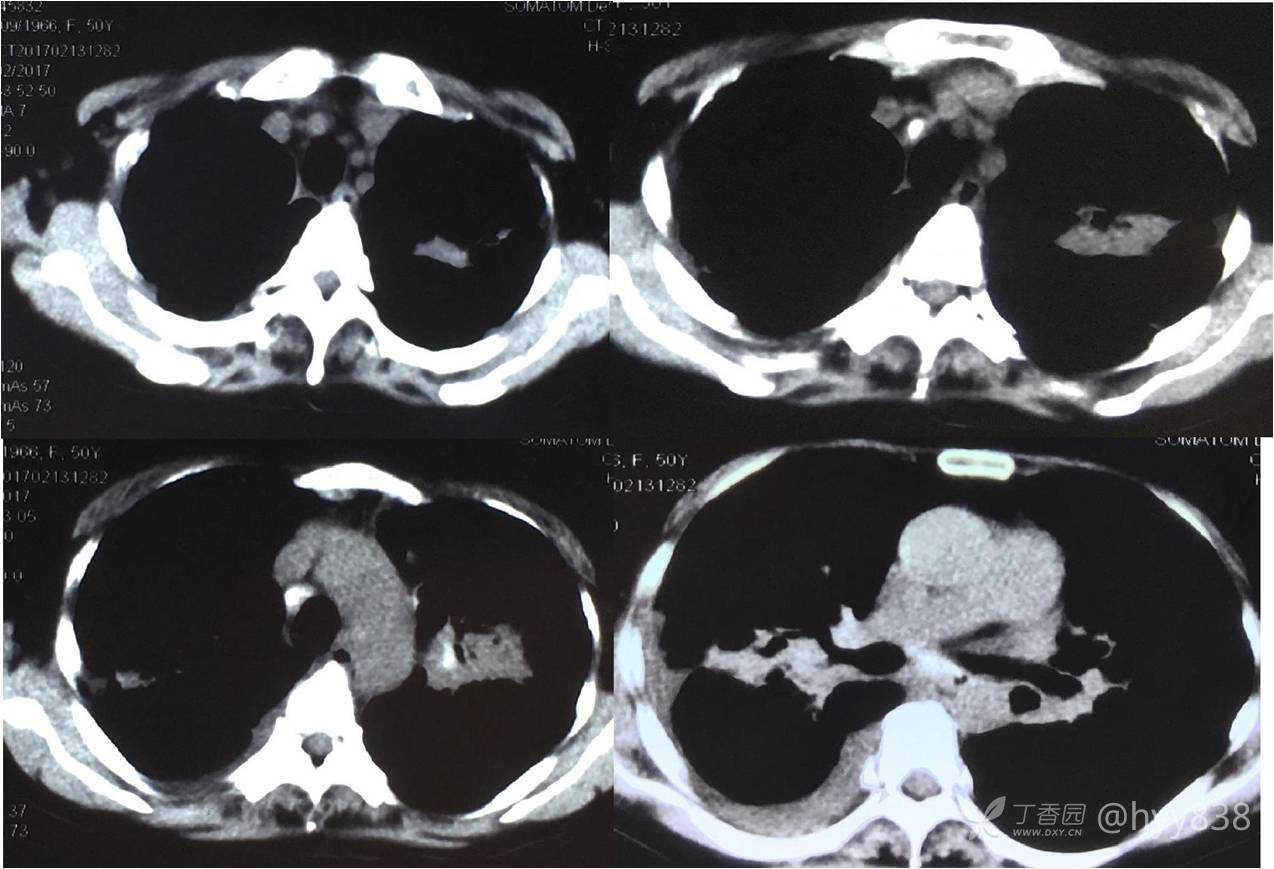

次年行CT复查,病灶进展

增强